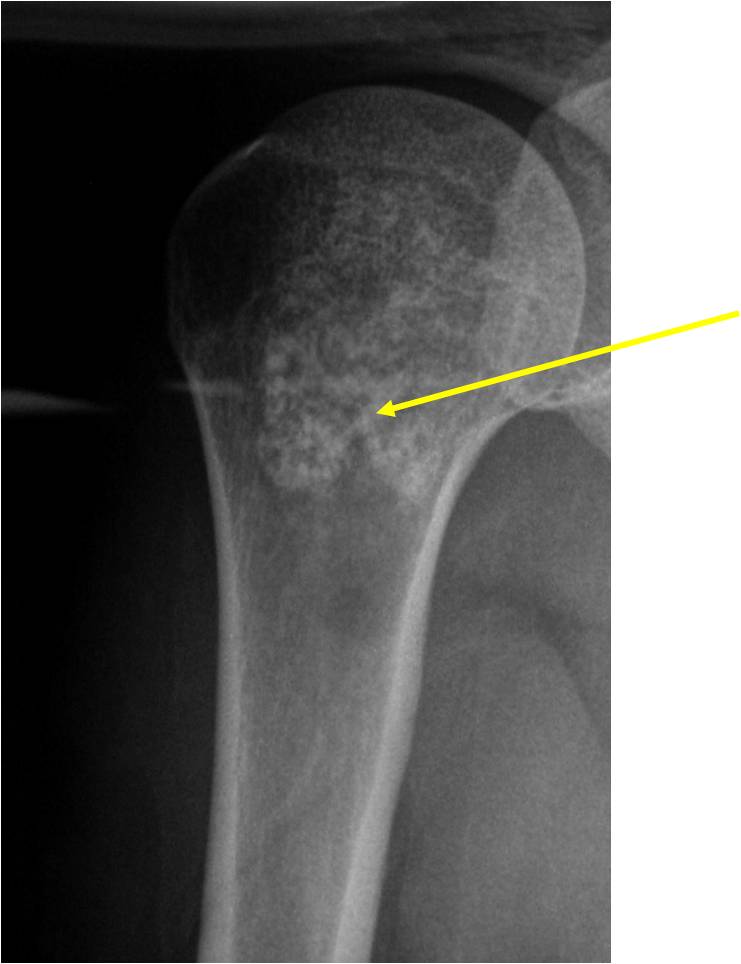

- Localized, radiolucent defect usually with punctate calcifications

- Calcifications are typical but not always present

- Matrix may demonstrate various degrees of calcification

- Calcifications are stippled, punctate, popcorn like calcifications and “Ring and Arc” calcifications

Plain X-Ray:

- Geographic lytic lesion

- Central often metaphyseal in long bones

- Can be eccentric also

- Expansile remodeling with thinned cortex

- Chondroid matrix with calcifications in majority of tumors

- Approximately 20% have limited or no calcifications

Ring and Arc Calcifications Minimal Endosteal Scalloping Cortex Intact No Soft Tissue Component No Periosteal Reaction

Ring and Arc Calcification No Endosteal Scalloping

Metaphyseal Tumor Heavy Calcifications Ring and Arc Pattern of Calcifications Minimal Endosteal Scalloping No Cortical Destruction No Periosteal Reaction No Cortical Destruction No Soft Tissue Component